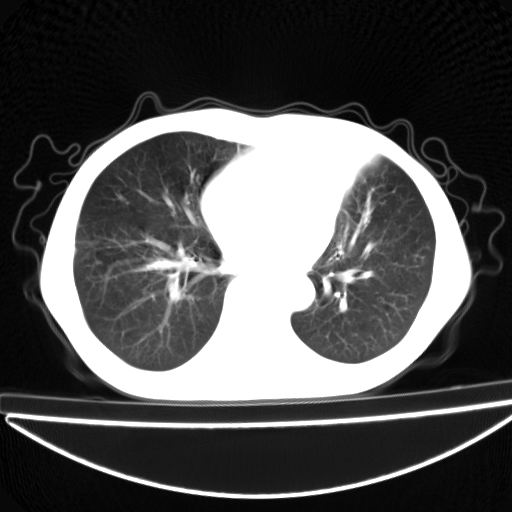

以下是引用杀毒软件在2009-4-28 17:58:00的发言:[br]考虑----左肺慢性肺脓肿形成继发上叶含气不良---抗炎后复查---待排肿瘤所致[br][br][本贴已被 杀毒软件 于 2009-4-28 18:01:26 修改过]